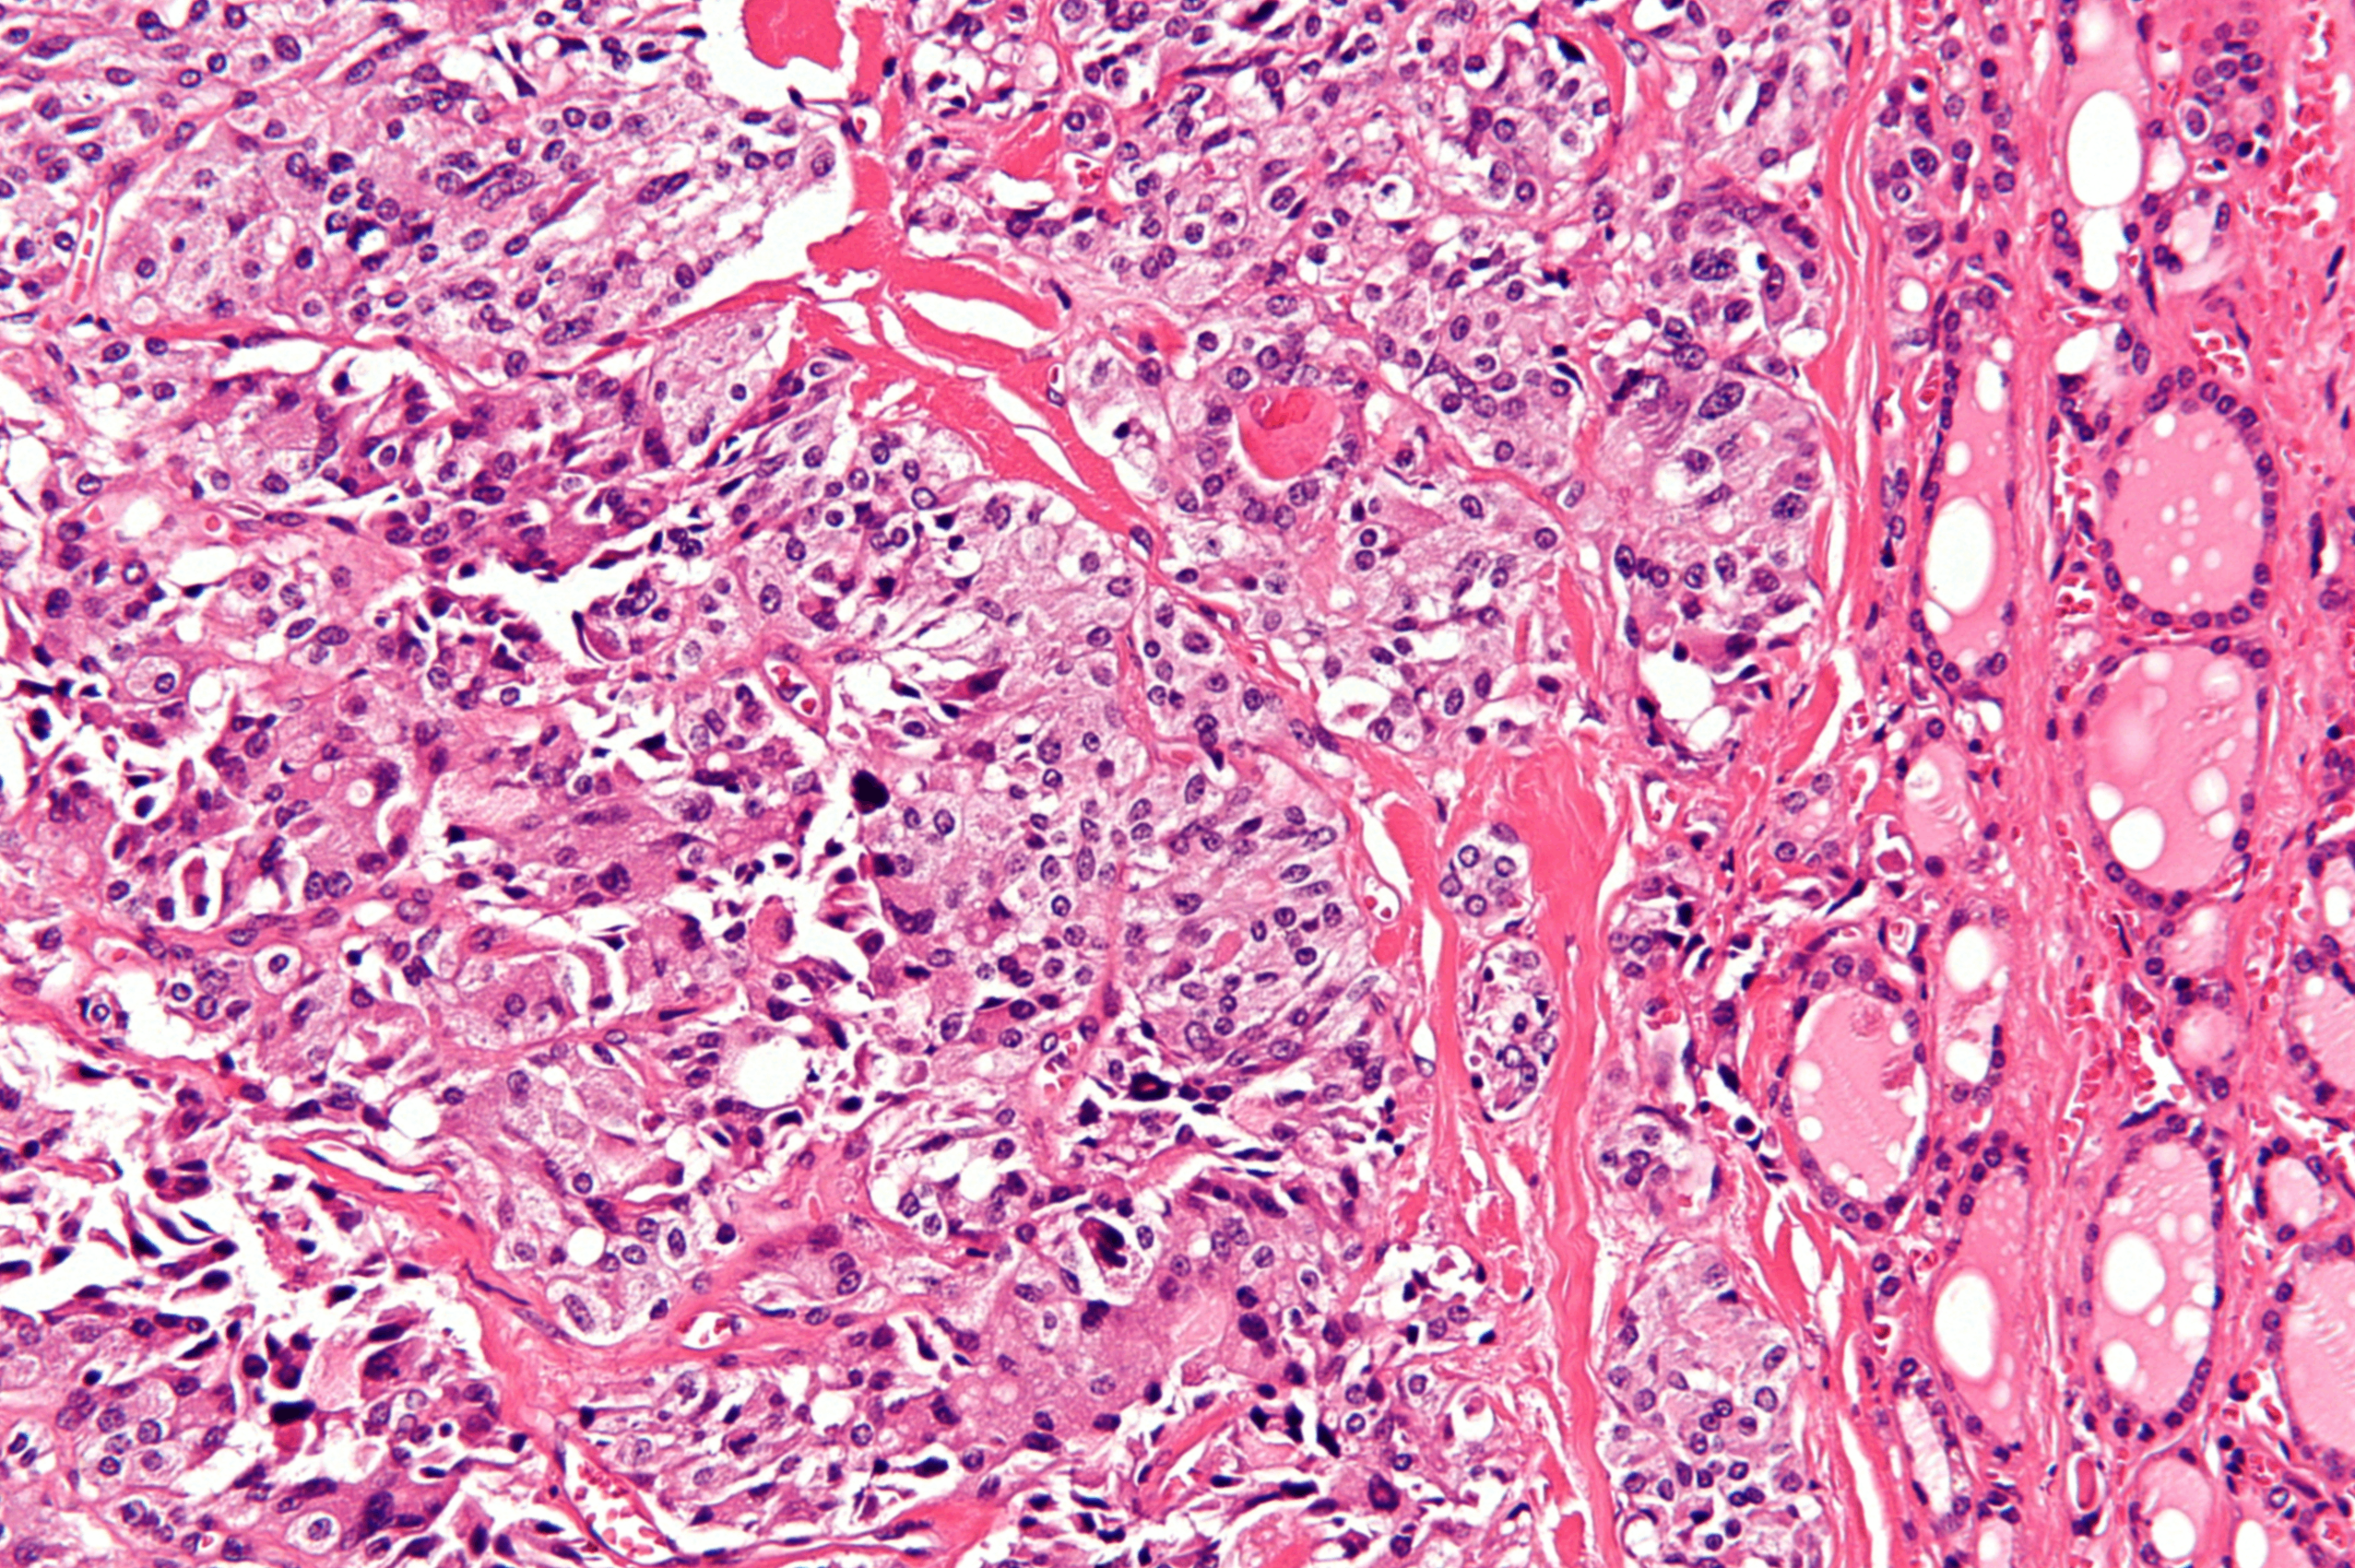

(2) 조직학적 소견

• 정상적인 여포성 분화가 매우 미미함

• 섬모(insular) 또는 기둥형(trabecular)의 성장 양상을 보임

종양 괴사가 흔히 동반함

• 역형성암종은 다음과 같은 세포 형태가 관찰됨:

- 다형성 거대세포; osteoclast-like multinucleate giant cell 또한 관찰됨

- 방추세포형

- 혼합형 (방추세포 + 거대세포 혼재)

Anaplastic thyroid carcinoma, Wikipedia Commons